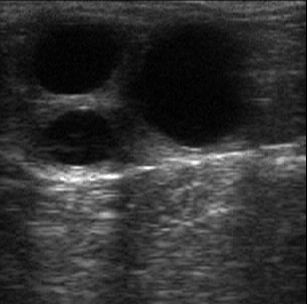

The birth of the Royal baby is still making the news headlines, so what better time to write about the use of veterinary ultrasound during equine pregnancy? Those that work within the equine field will be familiar with the problem surrounding the establishment of twin pregnancies, with the general consensus stating that twin pregnancies should be reduced wherever possible to avoid the possibility of damage to either the mare and/or the foal(s). As a consequence, embryo elimination is commonly carried out in such cases, making twin equine pregnancies somewhat of a rarity.

The establishment of a twin pregnancy can be detected with the use of veterinary ultrasound. There are a number of specialised veterinary scanning machines that can be used by practitioners to image the equine embryo, and it is important that the most suitable scanner is chosen. For more information on ultrasound scanners for use with the veterinary species, including the ranges available and the training required to use them, please visit a specialist veterinary ultrasound machine stockist.